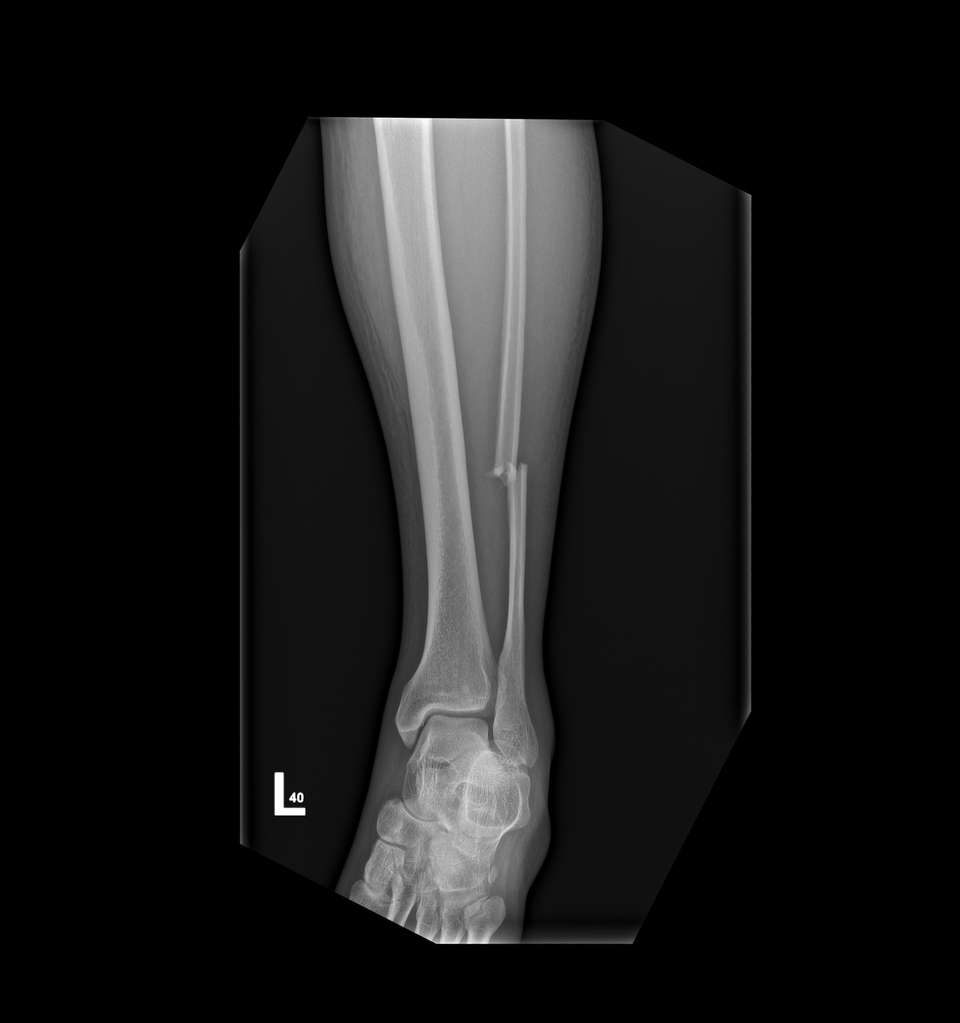

The Rugged Rides 6/24/2022The heart vibrates. 4 months ago my world changed, suddenly and brutally. A nightmare we never want to think of, dark and cold, got me. We were almost finishing a day, one of the first great trips, I was leading. Suddenly the world switched off, and I woke up in the hospital's ED. Despite extraordinary caution, despite years of experience. But how? I was looking in the mirror, I had my blinker on, I slowed down. This time it was not enough. A car surprised me from behind, overtaking us greedily, at a road intersection, against traffic, on a double continuous line. It slammed right into my sideway.